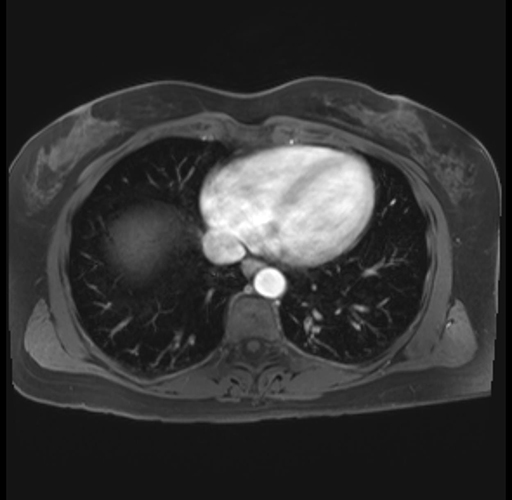

Imaging Analysis

Look through the patient's CT scan to identify any areas of concern for the necessary procedure.

Based on your CT findings, which issue(s) are present and would give reason for "planned slowing down moment(s)" in this case?